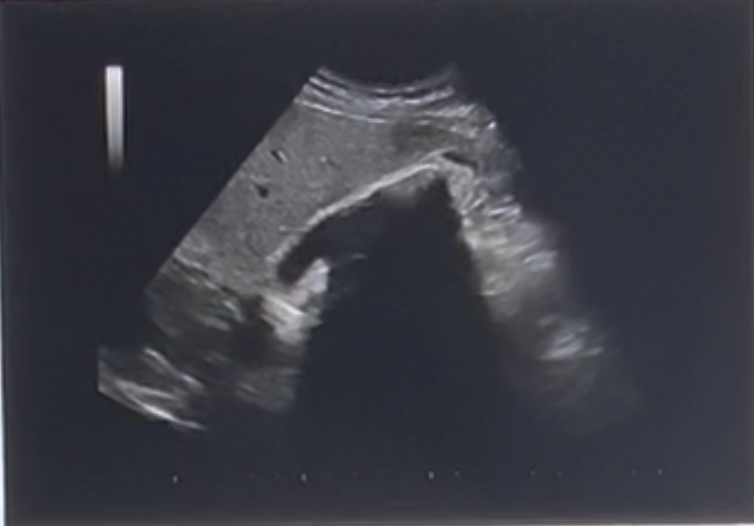

What artifact is demonstrated on the US image posterior to the gallbladder?

a. comet-tail artifact

b. clean posterior shadowing

c. dirty posterior shadowing

d. posterior enhancement

clean posterior shadowing